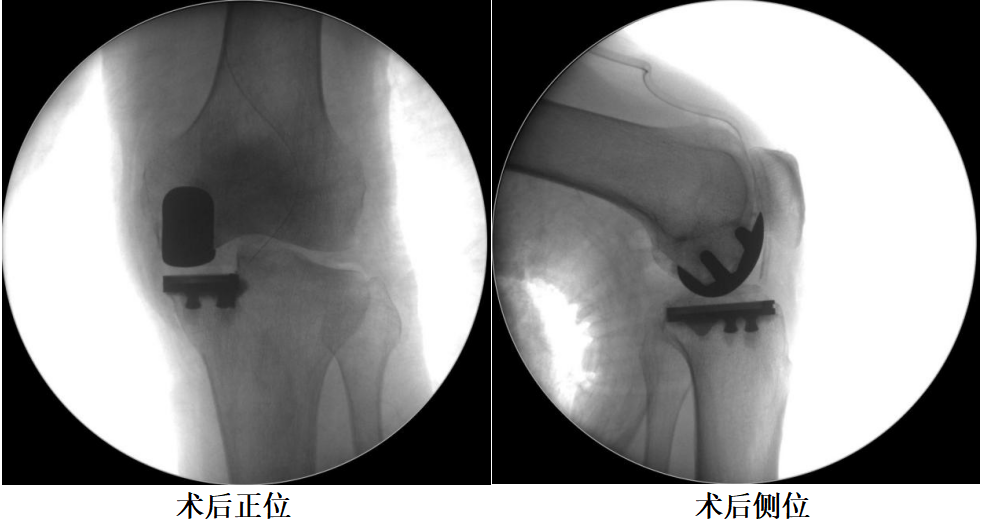

四、术后X透视片